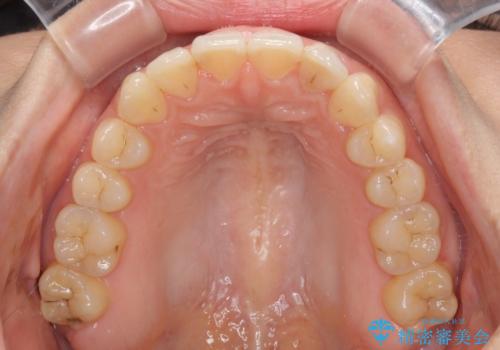

インビザライン矯正で前歯のデコボコを改善

- 前歯のデコボコを気にして来院された患者様です。

目立たないことを最優先にしたいとのことで、デコボコは軽度であったことから、インビザラインにて矯正治療を行うこととしました。

骨格的に下顎骨が左にずれており、上下の正中一致は困難ではありましたが、IPR(歯と歯の間を削る)や後方への移動など組み合わせて、できる限り改善しました。

インビザラインはマウスピースを外している時間が長いと、長期間使用しても前歯のデコボコはあまり改善されません。こちらの患者様は治療期間が長くなり、装着時間が短くなってしまったことで、気になる部分の改善により長期間を要するようになってしまいました。